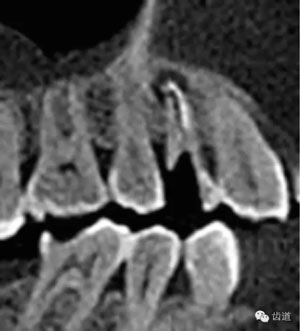

數(shù)碼x攝影顯示:近中頰根及腭根根管充填恰填,遠(yuǎn)中根管有遺漏。

檢查顯示:近頰及腭根充填恰填,遠(yuǎn)頰根管內(nèi)有少許充填物影像。根尖明顯低密度影像。

處理:顯微根管治療。放置橡皮障,去除暫封,顯微鏡下超聲去除頰側(cè)根管上段部分牙本質(zhì),探及遠(yuǎn)中根管口,見有糊劑遮蓋。Path file根管疏通,M Two根管預(yù)備至2506#,配合3%次氯酸鈉和17%EDTA超聲蕩洗,干燥根管,放置氫氧化鈣糊劑,zoe暫封。

處理:放置橡皮障,去除暫封,超聲結(jié)合2%CHX清除遠(yuǎn)頰根管內(nèi)氫氧化鈣糊劑,主牙膠試合后95%酒精沖洗干燥根管,結(jié)合AH Plus糊劑連續(xù)波熱牙膠垂直加壓充填根管,樹脂分層粘接修復(fù)牙體。建議定時(shí)復(fù)診進(jìn)行嵌體修復(fù),患者未執(zhí)行。